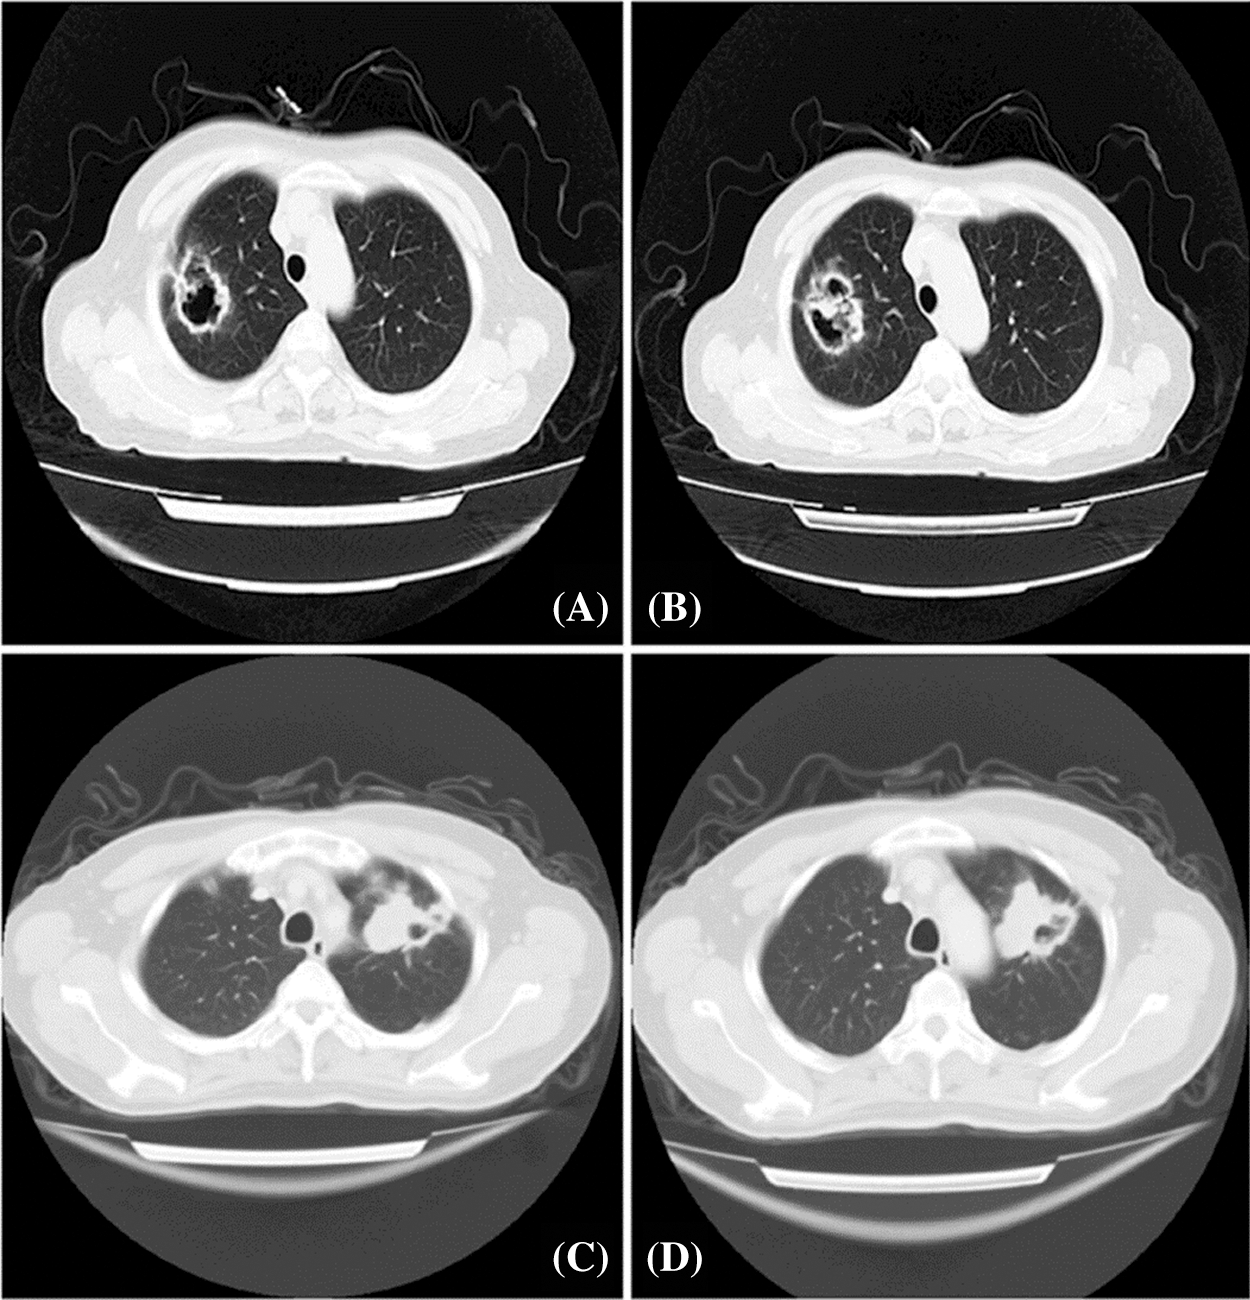

A total of 65 patients who were diagnosed with cavitary LUAD between September of 2005 and October of 2015 in the General Hospital of Central Theater Command Hospital, People’s Liberation Army of China, were included in the research. These patients had no chemotherapy and/or radiotherapy before surgical resection. All patients underwent a 64-row spiral CT scan with a slice thickness of 1.25 mm, 1.5 mm, or HRCT. Two radiologists (J. Liu and Y. Xue) independently examined and confirmed the imaging features of these samples. In accordance with previous studies, tumor cavitation was defined as an air-filled space with a wall thickness of ≤4 mm along its circumference [5,11,25,26] (Fig. 1).

Figure 1: Chest CT scanning presentation of patients with solitary cavitary lung cancer. A and B: The posterior segment of the upper lobe of the right lung showed an irregular and shallowly lobulated mass of 40 × 46 mm2 that was adjacent to pleura traction and depression with irregular cavity. Multiple nodules of varying sizes were observed. C and D: The anterior segment of the upper apex of the left lung showed a 46 × 55 mm2 soft tissue density shadow with eccentric cavity, which was lobulated and pulled by the adjacent pleura

The cavitation in the lungs was continually evaluated with the use of chest CT scans. Our results found solitary and thin-walled cavities, which localized at pulmonary periphery, and all these cavitary lesions demonstrated suspected signs of malignancy (Fig. 1).